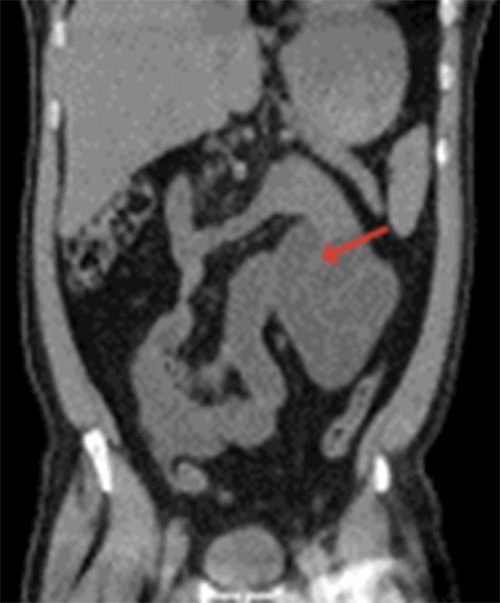

A noncontrast computed tomography (CT) scan of the abdomen obtained in the emergency department showed distended small bowel loops in the left upper quadrant that appeared clustered in the left pararenal space with mild crowding, congestion, and stretching of the mesentery suggestive of an internal hernia causing an acute intestinal obstruction (Figure 1). Given the presence of an acute abdomen, the patient was taken emergently to the operating room for abdominal exploration.

Figure 1. Coronal CT Scan of Abdomen. Published with Permission

A) Distended and clustered small bowel loops in left upper (arrow).

B) Crowding, congestion, and stretching of small bowel mesentery (arrow)